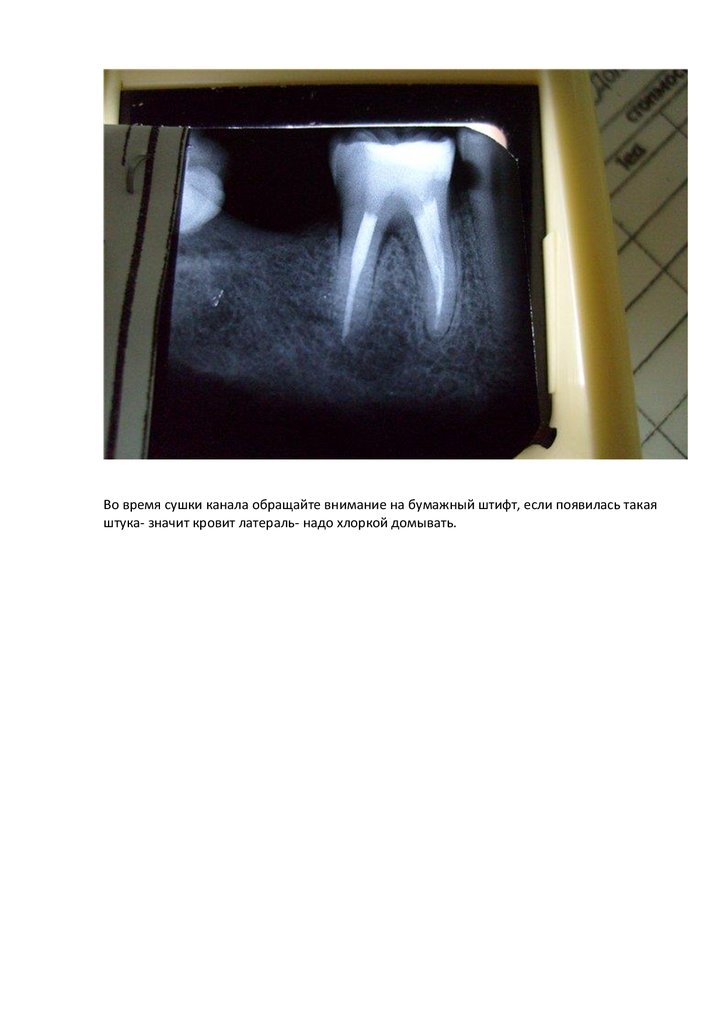

Во время сушки канала обращайте внимание на бумажный штифт, если появилась такая

штука- значит кровит латераль- надо хлоркой домывать.